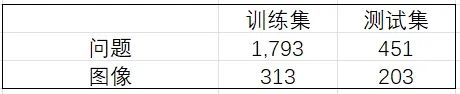

No.4 模型评测

在共451题的测试集中,模型Qwen2.5-VL-3B-Instruct微调前后的精确匹配率和语义相似度如下所示:

📌精确匹配度

我们将精确匹配度定义如下:

其中:

N:测试样本总数;

yi:第i个样本的标准答案;

yi^:模型预测结果;

Ⅱ:指示函数(完全匹配时取1,否则取0)。

该指标的特性在于:预测结果与标准答案需要完全一致。

📌语义相似度

我们将语义相似度定义如下:

其中:

N:测试样本总数;

yi:第i个样本的标准答案;

yi^:模型预测结果;

emb():是基于BGE模型(bge-large-zh-v1.5)的向量编码,它可以把自然语言编码为一个向量,即:emb(text)=BGE_Encoder(text)。

🚨注意:该评价指标将原本[-1,0)的数值进行了截断,只要是负相关的语义都给0分,得分只能是正相关的。